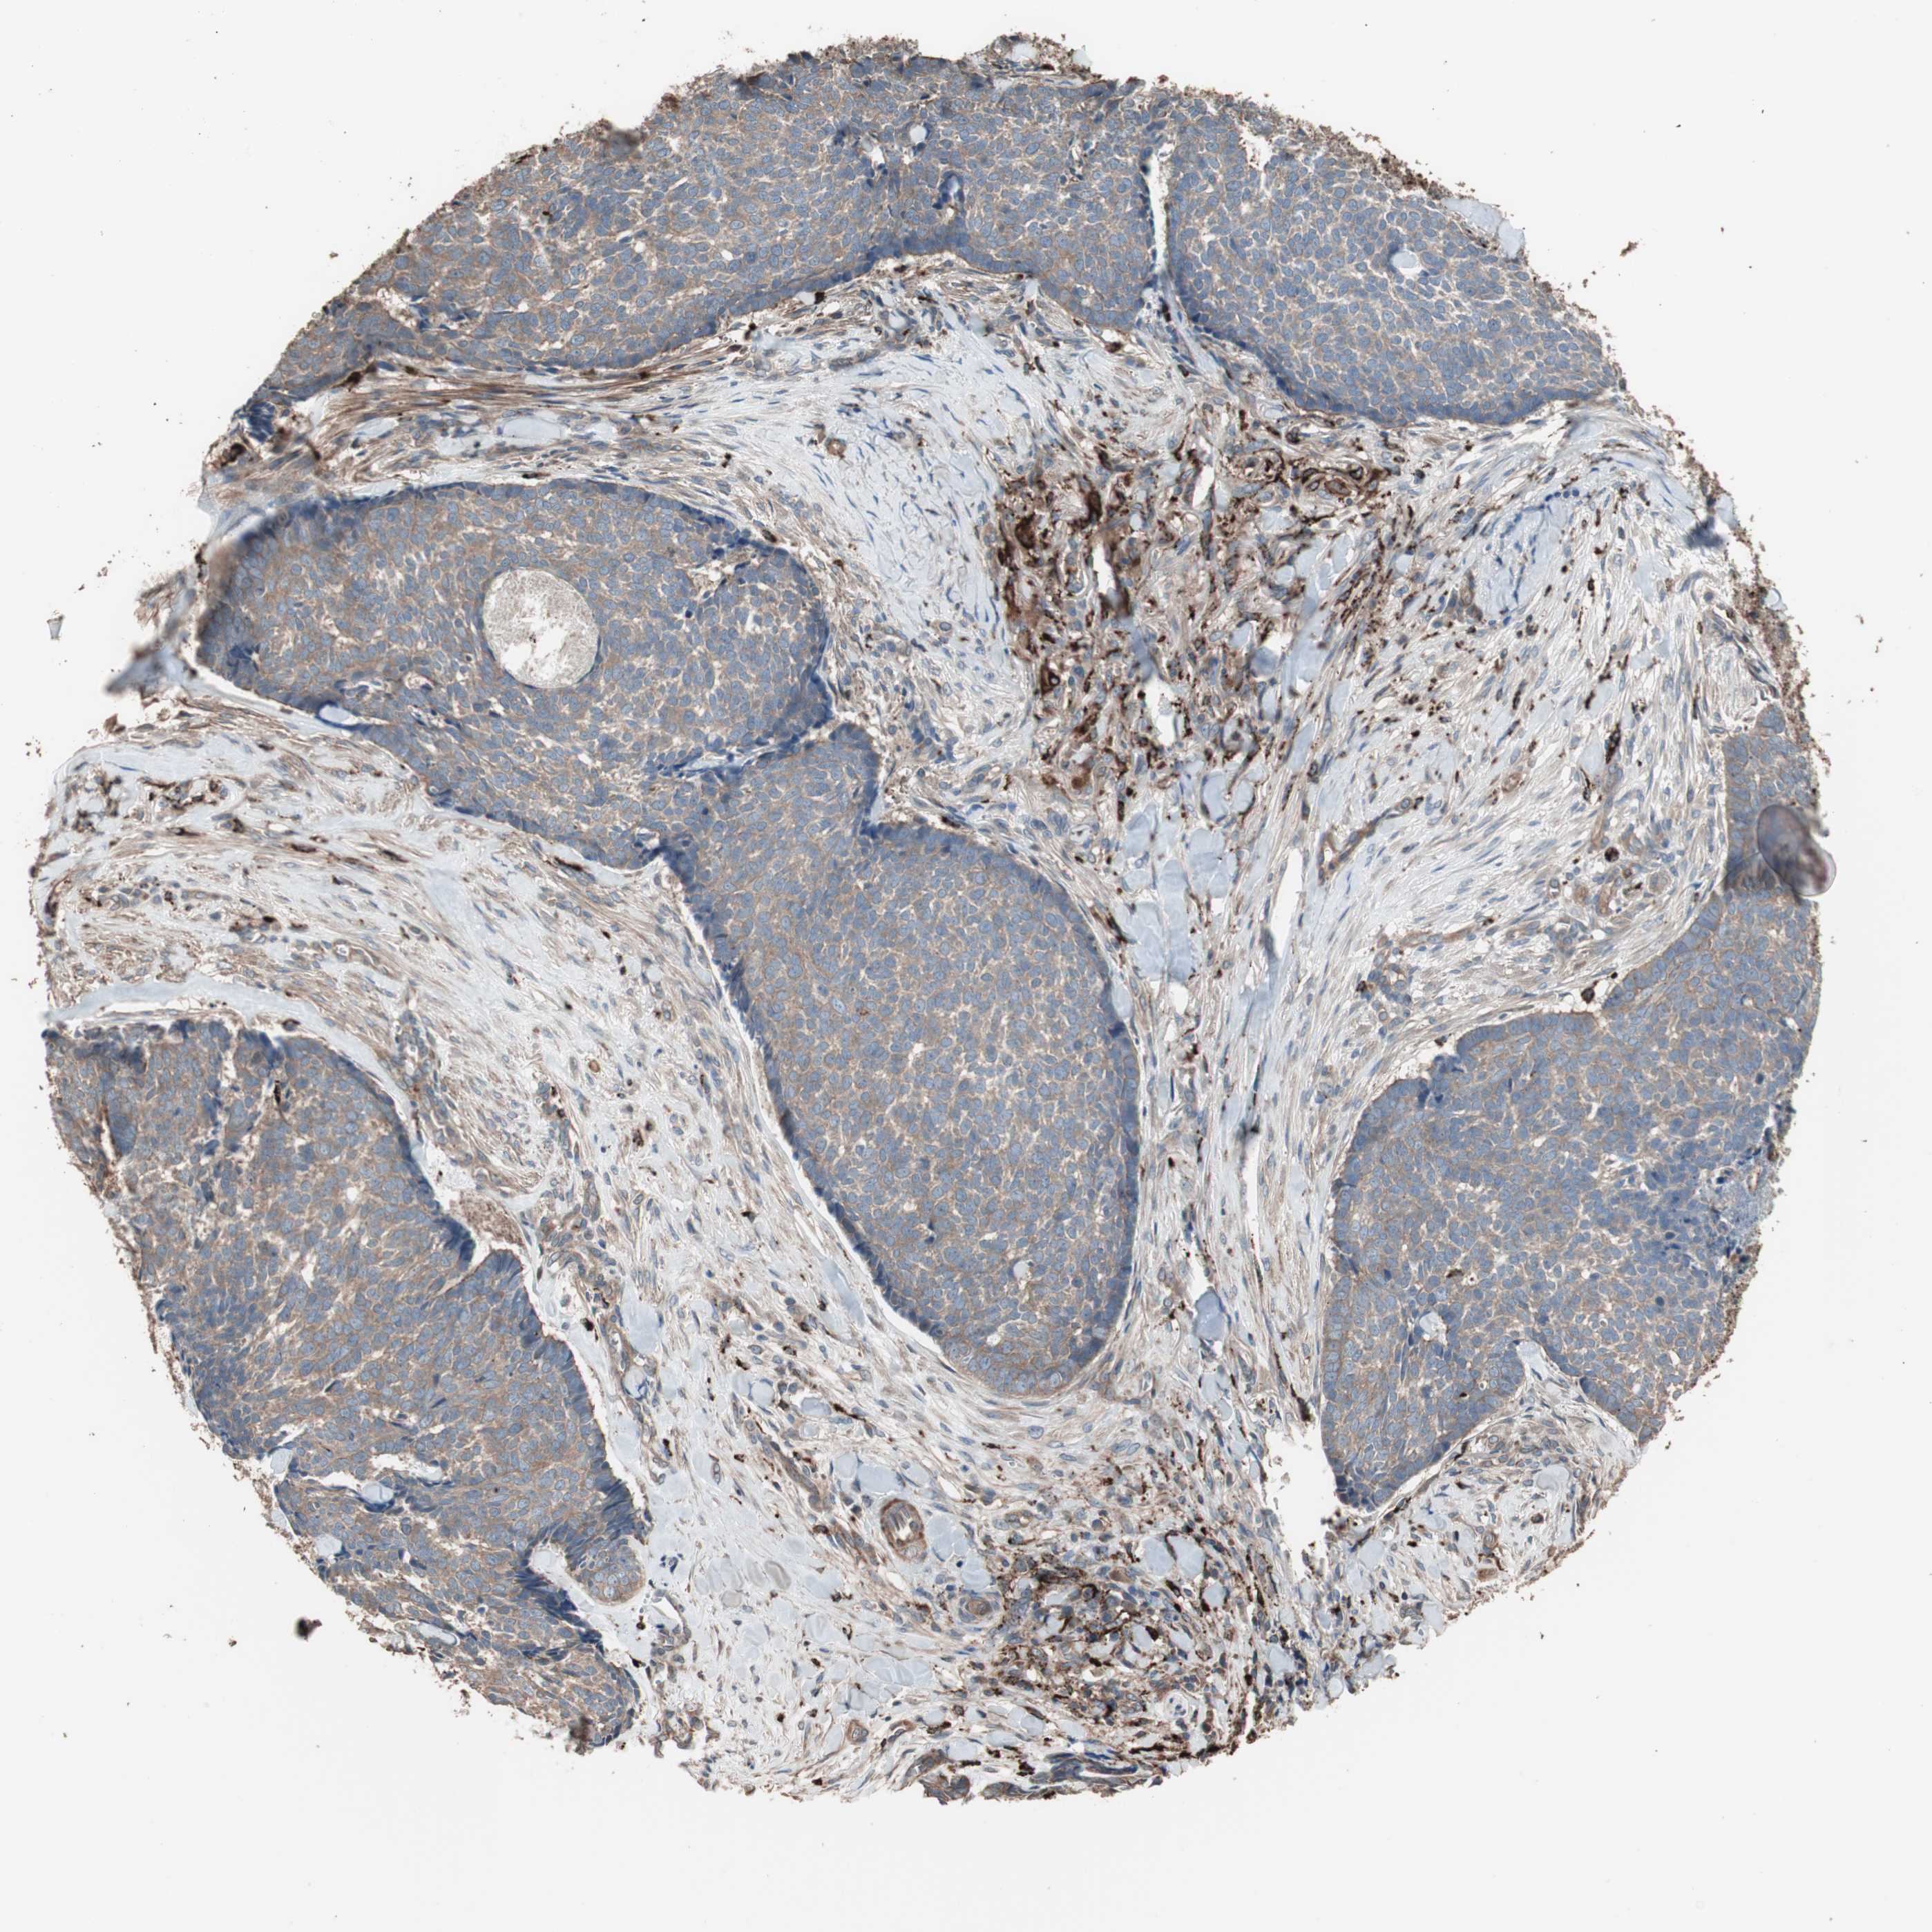

SKIN CANCER - Protein expressioni

A mouse-over function shows sample information and annotation data. Click on an image to view it in a full screen mode. Samples can be filtered based on level of antibody staining by selecting one or several of the following categories: high, medium, low and not detected. The assay and annotation is described here.

Antibody stainingi

Antibody staining in the annotated cell types in the current human tissue is reported as not detected, low, medium, or high, based on conventional immunohistochemistry profiling in selected tissues. This score is based on the combination of the staining intensity and fraction of stained cells.

Each image is clickable and will lead to virtual microscopy that enables deeper exploration of all samples and also displays staining intensity scores, fraction scores and subcellular localization as well as patient and tissue information for each sample.

Antibody HPA006543

Staining

High

Intensity

Strong

Quantity

>75%

Location

Nuclear

Squamous cell carcinoma, NOS